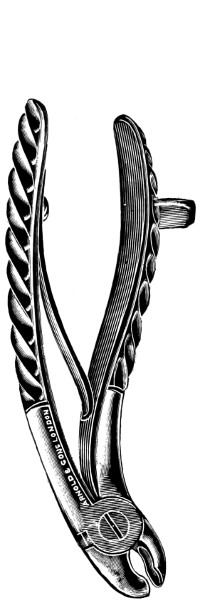

Fig. 13. Keen-Hoffmann’s Craniectomy Forceps.

Fig. 16. De Vilbiss’s Craniectomy Forceps.

Previous to any attempt at enlargement of the trephine hole, the dura mater must be separated from the bone with the aid of Horsley’s dural separator or other suitable instrument. Of the many patterns of craniectomy forceps, the following will be found to suit all requirements:—

The visceral blade is introduced between the dura and the bone and ‘morcellement’ carried out. It is essential[25] that the surgeon should not be too greedy, resting content with the removal of small fragments at a time.

They possess great mechanical advantage and are mainly suited for the rapid removal of large portions of bone.

This instrument is mainly utilized in the smoothing and refreshing of sharp edges of bone, and in the ‘morcellement’ of the thinner portions of the skull—temporal and cerebellar regions.

A clever contrivance whereby the operator is enabled to cut a narrow channel in the bone. Mainly utilized in the formation of the osteoplastic flap.

The dura is now separated from the bone along the line of the two vertical incisions, and the visceral blade of de Vilbiss’s forceps insinuated beneath the bone, starting at one trephine-hole and working downwards to the lower limit of the incision. It is essential that the operator should be satisfied with the ‘morcellement’ of small portions of bone at each bite of the instrument. At the lower end of each[28] of the vertical incisions the forceps is directed inwards for 1⁄4 to 1⁄2 inch so as to weaken the base of the flap.